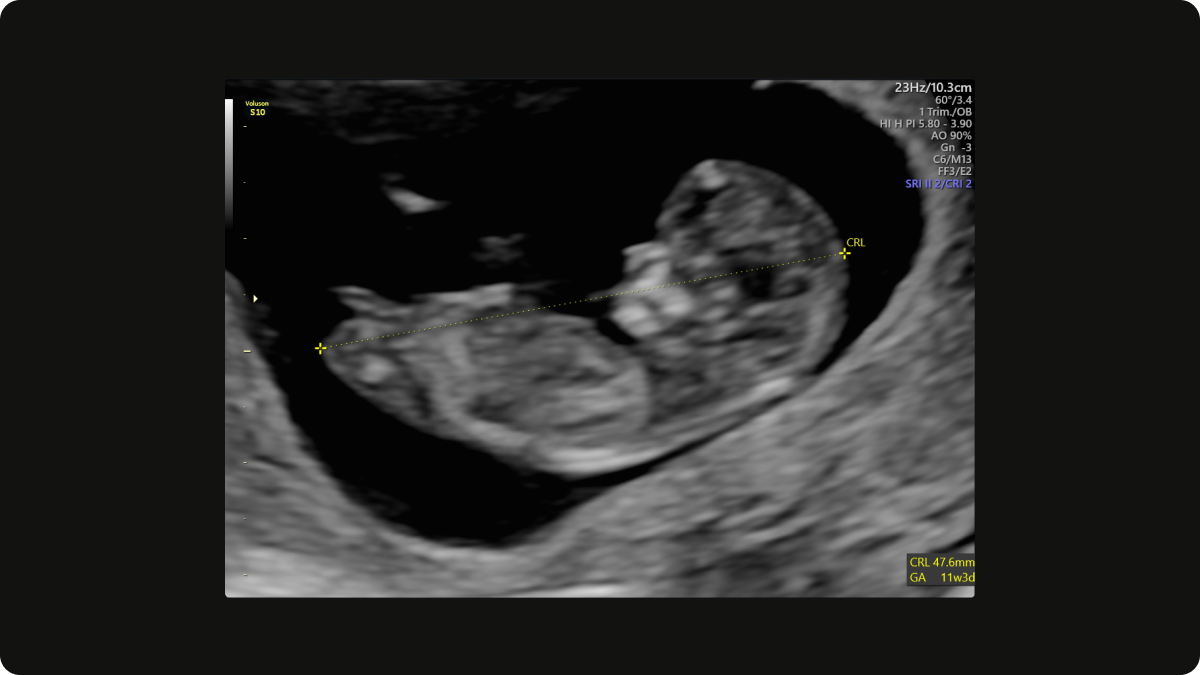

An example of what you can see on an Early Pregnancy Scan at 12 weeks gestation.

At this stage, your baby is still very small—but there’s so much we can see:

- Size of baby (CRL – crown-rump length)

- Confirmation of how many weeks pregnant you are